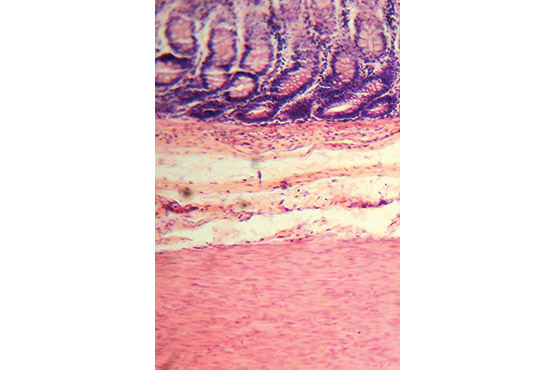

Vėžys paprastai atsitinka vidiniame žarnos sluoksnyje, auglys kemša spindį, perauga sienelę į išorę ir gretimus organus, plinta kraujagyslėmis ir limfagyslėmis atokiau. Paprastai žmogus pastebi du dalykus. Pirmasis – pasikeičia tuštinimasis. Ne vienkartinai ir staiga, o palaipsniui, keletą savaičių, ir blogėjančiai. Gali skaudėti tuštinantis, gali užkietėti viduriai, gali pūsti vidurius, paviduriuoti, gali atsirasti neproduktyvus varymas tuštintis, gali pasikeisti tuštinimosi ritmas. Ir visa tai be akivaizdžios priežasties. Antrasis požymis – kraujas išmatose. Nebūtinai šviežias paviršiuje, dažniau tamsus ir susimaišęs. Kiti požymiai – mažakraujystė ir silpnumas, pilvo skausmas, liesesni užsičiuopia guzą pilve, blogas apetitas…